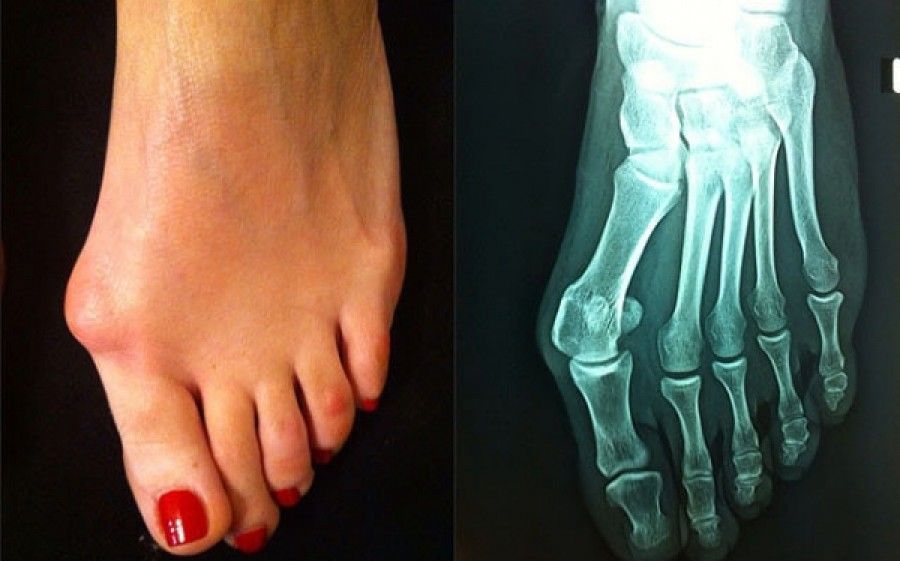

Όταν εμφανίζεται το κότσι, το μεγάλο δάκτυλο αλλάζει κατεύθυνση, παρεκκλίνει προς τα έξω σε σχέση με τα υπόλοιπα δάκτυλα ενώ το 1ο μετατάρσιο παρεκκλίνει προς τα μέσα. Αυτό έχει σαν αποτέλεσμα το μεγάλο δάκτυλο να πιέζει και να συμπαρασύρει τα υπόλοιπα δάκτυλα, τα οποία με τη σειρά τους παρεκκλίνουν και αυτά προς τα έξω, και η κεφαλή του 1ου μεταταρσίου να δημιουργεί ένα εξόγκωμα στο έσω χείλος του ποδιού.

Σταδιακά η παραμόρφωση εντείνεται, το μεγάλο δάκτυλο εφιππεύει το 2ο δάκτυλο (σπανίως μπαίνει κάτω από το 2ο δάκτυλο), το δέρμα στο σημείο του εξογκώματος (που προκαλεί η κεφαλή του 1ου μεταταρσίου) γίνεται εξέρυθρο και επώδυνο διότι λόγω της πίεσης που δέχεται από το υπόδημα φλεγμαίνει το δέρμα και ο θύλακος της άρθρωσης με αποτέλεσμα να δημιουργείται εξόστωση στην κεφαλή του 1ου μεταταρσίου. Σε βάθος χρόνου παραμορφώνονται τα υπόλοιπα δάκτυλα, γίνονται γαμψά (σφυροδακτυλία) και δημιουργούνται κάλοι στην ραχιαία επιφάνειά τους. Δημιουργούνται επίσης κάλοι στην πατούσα λόγω αλλαγής της ανατομίας και πτώσης των υπόλοιπων μεταταρσίων. Αλλάζει εν γένει όλη η ανατομία του άκρου ποδός, γεγονός το οποίο εκτός από το ακαλαίσθητο αποτέλεσμα προκαλεί πόνο και δυσχέρεια στη βάδιση.